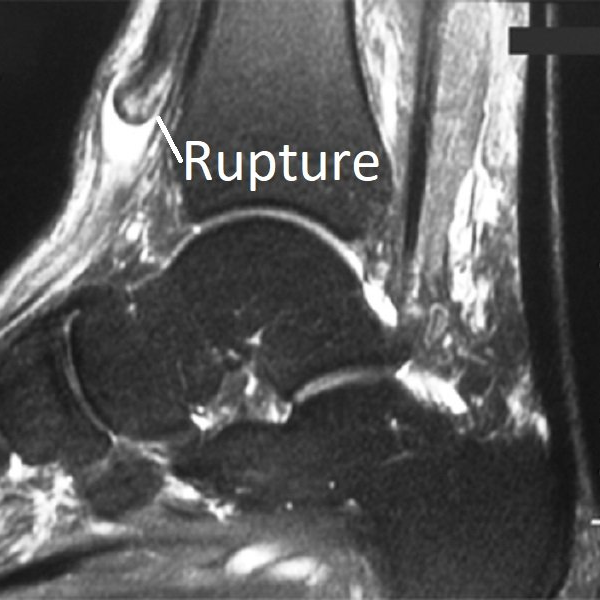

Tibialis Anterior Complete Rupture

Like the Achilles tendon

and peroneal tendons, the tendon of tibialis anterior can completely rupture.

Interestingly, this event can be without injury (spontaneous). Mild transient pain occurs, a swelling

appears in front of the ankle (“pseudo-tumour”), and a foot-drop gait

develops. The toe extensor tendons are recruited to help lift the foot which can cause "clawing". Surgery is not always required (see below) and is more complex than just sewing the tendon ends together.

How are Tibialis Anterior Tendon Problems Diagnosed?

Investigations commonly arranged are:

- ultrasound and/or MRI scan of the foot